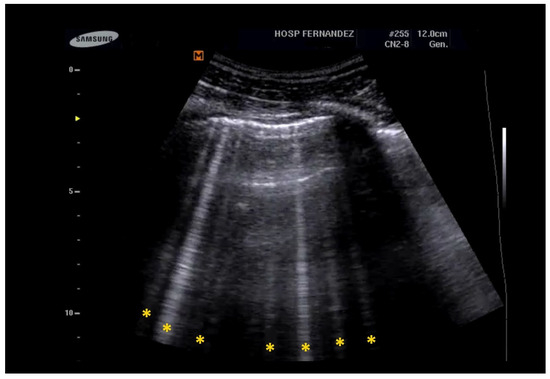

- Multiple B-Lines: These appear in a diffuse, inhomogeneous distribution and are critical for ILD diagnosis.

- Pleural Line Abnormalities: These may include thickening, irregularities, and fragmentation of the pleural line.

- Anterior subpleural consolidations;

- Absent or reduced lung sliding;

- “Preserved areas” of normal lung parenchyma;

- Abnormalities in the pleural line (e.g., fragmented, thickened, or irregular pleural line);

- Inhomogeneous distribution of B-lines.